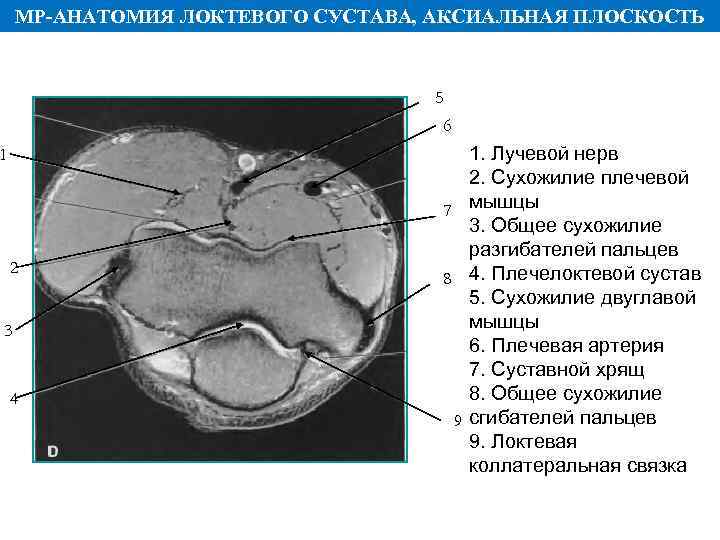

МР АНАТОМИЯ ЛОКТЕВОГО СУСТАВА, АКСИАЛЬНАЯ ПЛОСКОСТЬ 5 6 1 2 3 4 1. Лучевой нерв 2. Сухожилие плечевой 7 мышцы 3. Общее сухожилие разгибателей пальцев 8 4. Плечелоктевой сустав 5. Сухожилие двуглавой мышцы 6. Плечевая артерия 7. Суставной хрящ 8. Общее сухожилие 9 сгибателей пальцев 9. Локтевая коллатеральная связка

МР АНАТОМИЯ ЛОКТЕВОГО СУСТАВА, АКСИАЛЬНАЯ ПЛОСКОСТЬ 5 6 1 2 3 4 1. Лучевой нерв 2. Сухожилие плечевой 7 мышцы 3. Общее сухожилие разгибателей пальцев 8 4. Плечелоктевой сустав 5. Сухожилие двуглавой мышцы 6. Плечевая артерия 7. Суставной хрящ 8. Общее сухожилие 9 сгибателей пальцев 9. Локтевая коллатеральная связка